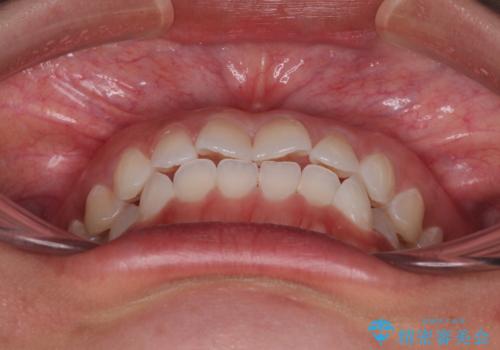

- 上下前歯のデコボコを気にして来院された患者様です。

ワイヤー矯正でもマウスピース矯正でも可能でしたが、短期間で、自身の手を煩わせることなく治療を行いたいとのことで、ワイヤー装置にて矯正治療を行うこととしました。

僅か半年強、あっという間に治療を終えることができました。